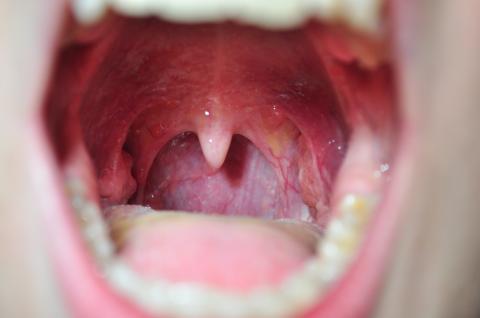

Pro větší náhled klikněte na obrázek

Zdravím,už odmala trpím na různé škrábání v krku, nicméně moje obvodní lékařka vždy říká, že to nic není... Na nějakou dobu se to zlepšilo, ovšem zhruba v listopadu minulého roku jsem prodělala pořádnou chřipku (byla jsem doma 2 týdny) a od té doby mě soustavně škrábe v krku, jsem nesmírně unavená, mám zvětšené krční uzliny, bolí mě hlava a mívám zvýšenou teplotu nebo je mi naopak hrozná zima (nemůžu se zahřát, mám ledové ruce i nohy a nízký tlak - 80/60). Každý měsíc se to zhorší - strašná únava, škrábání v krku, bolesti kloubů, svalová slabost a třes, až nakonec na dva dny ulehnu úplně, přičemž mi je opravdu špatně s teplotou (max. 38.5°C).Vzhledem k tomu, že to už opravdu narušuje moje povinnosti a normální život, stejně jako naprostá zoufalost (moje doktorka říká, že je to v pohodě. Když jsem naposledy opravdu naléhala, vzala mi krev a udělala výtěr -> vše v naprostém pořádku)...Teď užívám ribomunyl, ale zatím jen krátkou dobu.Alergie nemám (vyšla mi jen slabá na trávy), všechno mám jinak v pořádku. - Zhruba od ledna mám výtoky a svědění - na gyndě mi dali jenamazol a po pár dnech je to lepší, tak to asi nesouvisí, ale radši doplňuji pro celistvost -Možná to nějak souvisí, ale už odmala mi především ráno opravdu hodně smrdí z úst a velmi často vykašlávám jakési hnisavé(?), smrduté hrudky, které se mi drží na mandlích.Co se krku týče, na kořeni jazyka mám soustavně takové velké bulky a bělo-šedavý povlak, který se táhne až ke krajům jazyka. Celou pusu mám zarudlou (výrazné žilky či co to je), občas mě i pálí rty. Bolest postupuje až směrem do nosu. Po ránu to bývá horší.Opravdu moc děkuji za jakoukoli pomoc nebo nápad, jsem opravdu zoufalá.

Dobrý den, podle fotky mi připadá Vaše dutina ústní v pořádku. Symptomy, které uvádíte, mi připomínají symptomy EB virosy (Epstein-barr virus) nebo CMV (cytomegalovirus), které vyvolávají mononukleózu. Ta se může projevit i jako angína. Jestli krevní testy máte v pořádku, i výtěr z krku, tak bych se spíš přikláněla k této virové infekci. Protilátky se dají zjistit z krve, ale nijak se to neléčí, antibiotika na virovou infekci nejsou účinné. Virus s krve nikdy nezmizí, takže v případě stresu, poruchy imunity, nebo těžší nemoci, se virus může opět probudit a projevit se tím, že Vám způsobí únavový syndrom. Důležitý je klid na lůžku, omezení sportovních aktivit, dostatek tekutin.